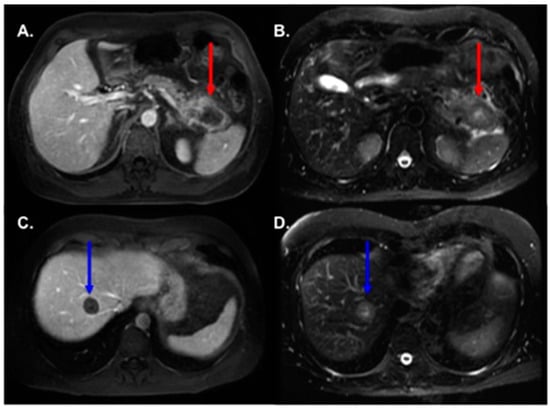

3.2. MRI Findings